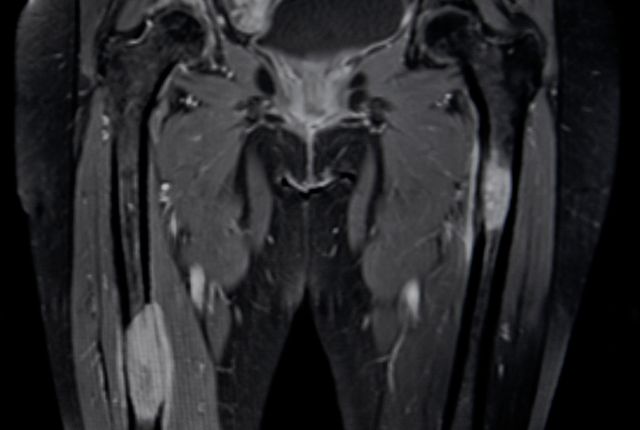

une IRM pelvienne ou une uro-IRM si l'uroscanner est contrindiqué;